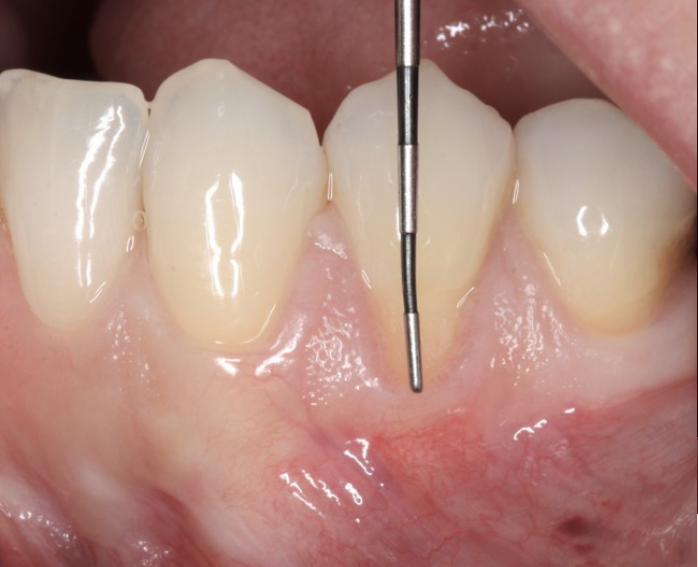

Esta especialidade também é responsável pela recuperação de recessões gengivais, dependo da situação poderá ser possível reposicionar a gengiva na sua posição natural. No entanto, apenas com um diagnóstico médico é possível identificar o prognóstico da situação.